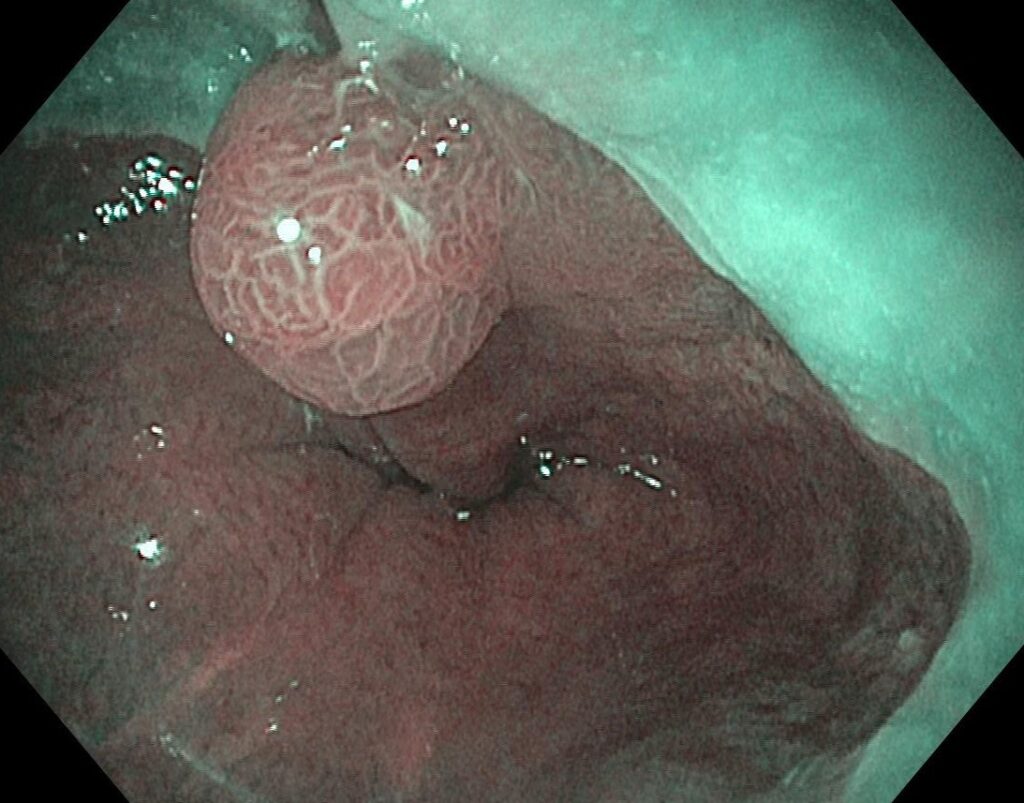

嚥下障害を有する患者さん:内視鏡観察では食道胃接合部にショートバレット粘膜とその境界に腫瘍を認めます。

NBI(狭帯域光観察)では悪性所見は認めませんが、有症状のため、治療適応と診断しました。

嚥下障害を有する患者さん:内視鏡観察では食道胃接合部にショートバレット粘膜とその境界に腫瘍を認めます。

NBI(狭帯域光観察)では悪性所見は認めませんが、有症状のため、治療適応と診断しました。